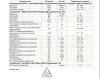

ШикТест энантат PL 125мг 1 раз в 4 дня.

Анализ после 4ой инъекции через 24 часа.